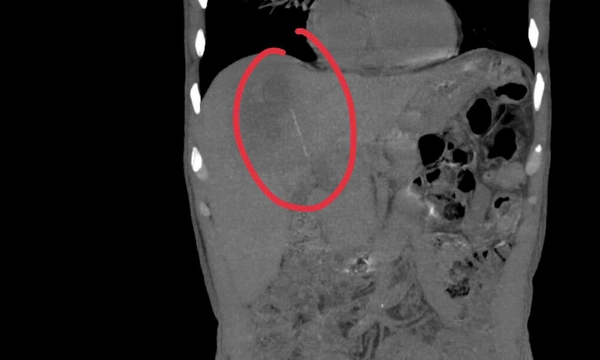

BS.CKI Mã Phước Nguyên – Phó Trưởng khoa Nội Tiêu hóa bệnh viện Chợ Rẫy cho biết, qua khám lâm sàng và tiến hành siêu âm bụng, các bác sĩ ghi nhận hình ảnh ổ áp xe gan, tuy nhiên, điểm bất thường là ổ áp xe nằm khá sâu, biểu hiện không điển hình. Vì vậy, bệnh nhân được chỉ định nhập viện để làm thêm các cận lâm sàng chuyên sâu.

Khi tiến hành siêu âm kỹ hơn, ê kíp phát hiện một dị vật cản quang xuyên trong nhu mô gan, chiều dài ước tính khoảng 6-7cm. Ngay sau đó, bệnh nhân được chỉ định chụp cắt lớp vi tính (CT scan) ổ bụng.

Kết quả cho thấy có một dị vật dạng que dài nằm hoàn toàn trong nhu mô gan, kèo theo ổ áp xe sâu. Trước nguy cơ biến chứng nặng nếu không điều kịp thời, ê kíp khoa Nội tiêu hóa đã nhanh chóng hội chẩn cùng khoa Ngoại Gan Mật Tụy, thống nhất phương án phẫu thuật lấy dị vật, dẫn lưu ổ áp xe, kết hợp điều trị kháng sinh phù hợp.